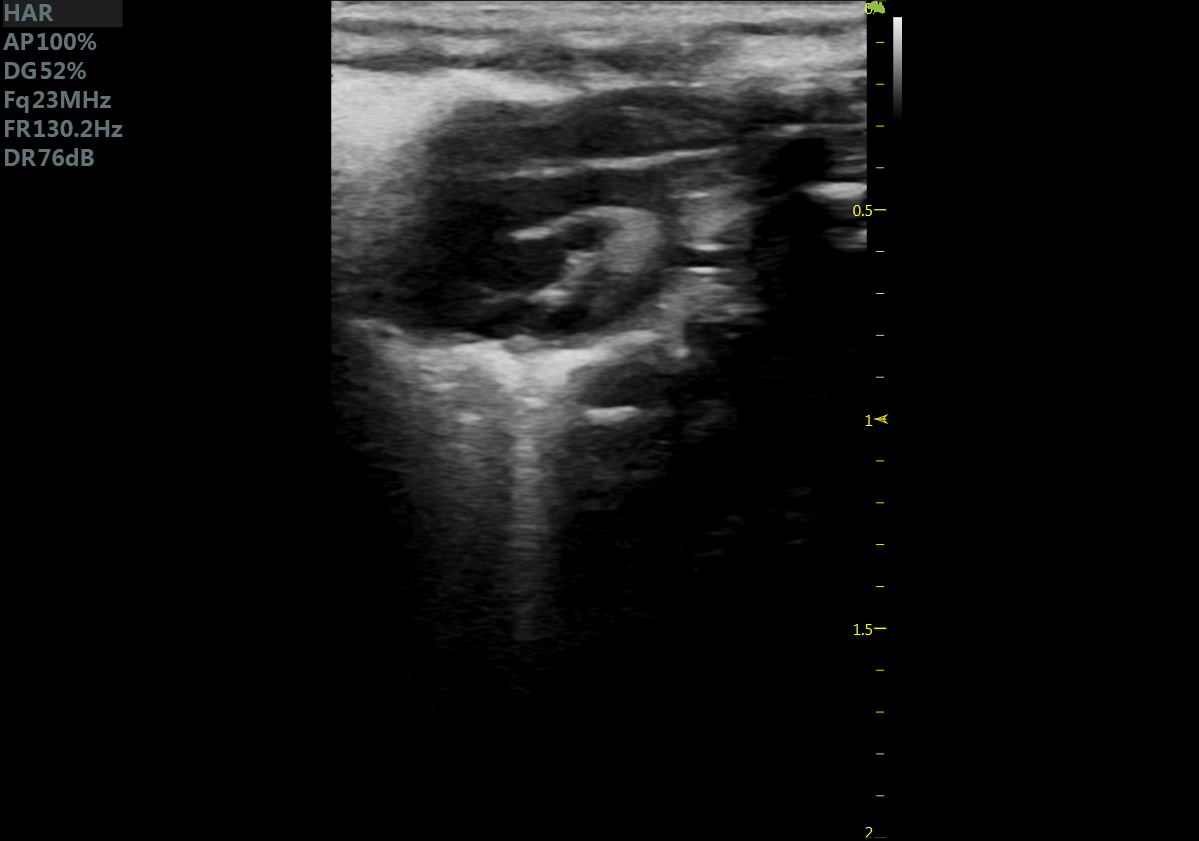

小鼠长轴M型 小鼠短轴M型

小鼠长轴B型 小鼠短轴B型

小鼠主动脉弓 小鼠肾脏血流

小鼠乳头肌水平 小鼠肝脏

大鼠短轴M型 大鼠长轴M型

大鼠长轴B型 大鼠主动脉弓

大鼠胎鼠心脏血流 大鼠心尖四腔

大鼠肝脏 大鼠肾脏